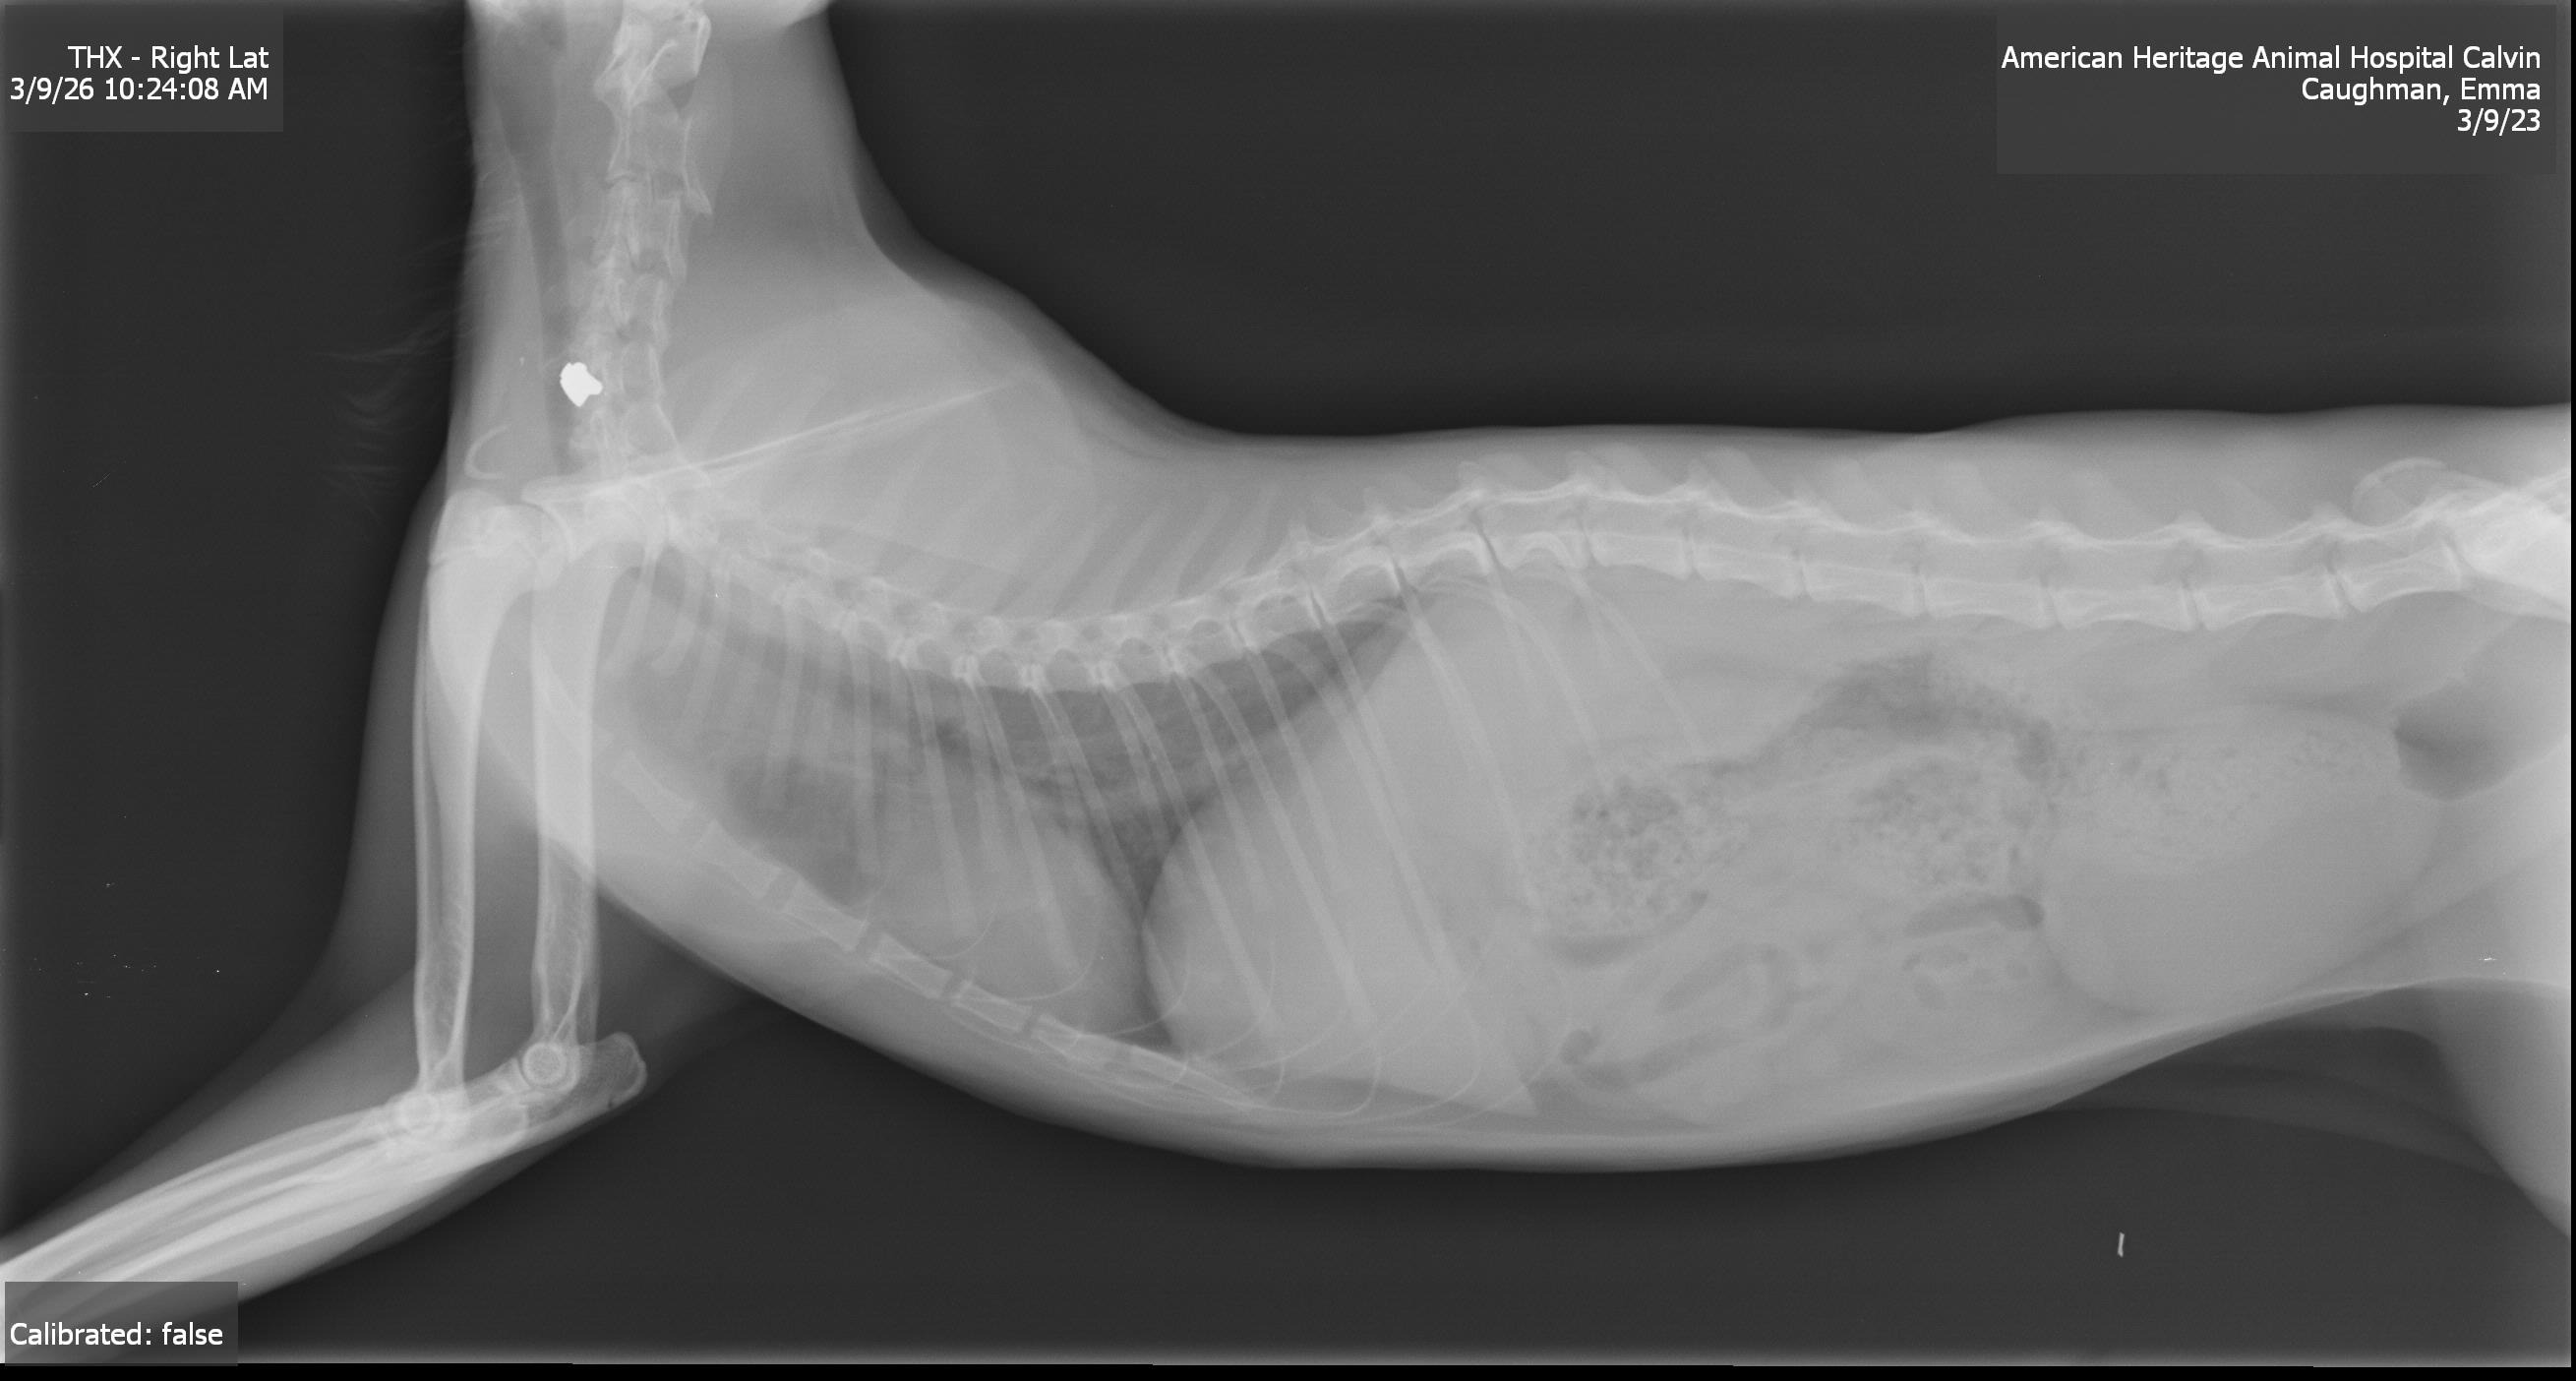

This is Calvin. One of our neighbors shot him. Calvin is one of the neighborhood strays in our community, and we've fed and cared for him since he was a kitten. Since he grew up around us, he's very social and super friendly—honestly, I've never met a cat this sweet. On Friday, we found him crawling up to our door, stumbling and dragging his front leg, with a bloody wound on his neck. We assumed he'd broken his leg and thought he'd been attacked by something or possibly hit by a car. But after taking him to the vet, we learned that what he went through was much, much worse. The vet took an X-ray, which showed a bullet lodged in his spine. The bullet barely missed his artery and is only a hair away from his spinal cord. They believe that it's damaged a nerve that has affected his ability to move and feel his leg. His prognosis is uncertain, as surgery to remove the bullet would cost thousands of dollars, which we don't have. Now, all we can do is wait and see what happens. If the bullet migrates, he could become completely paralyzed and would have to be euthanized. We've already spent a lot in vet bills, and as much as we'd love to get him surgery to remove the bullet, we simply can't afford it. We're trying to raise money to give him the best chance of survival. If he doesn't make it, we will use any funds raised to TNR the remaining community cats. We love Calvin and want to give him the best chance at life. Any support, no matter how small, will make a difference for him and our community cats. Please help us save Calvin and support our neighborhood strays.